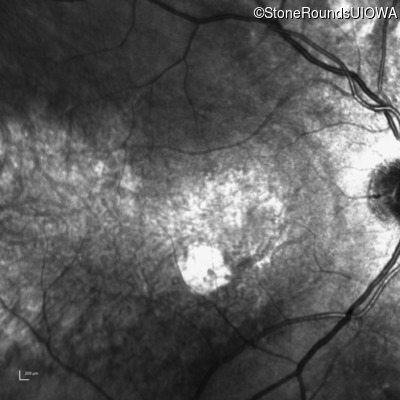

Fluorescein Angiography - Right - 20/300 sc

Exemplar